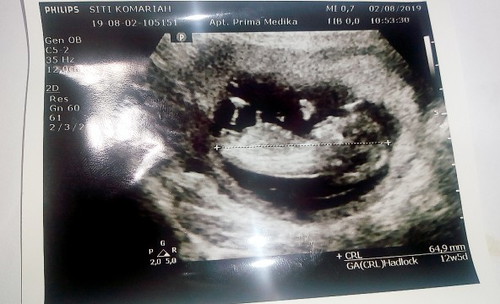

alhamdulilah bunda" saya tadi usg ddek nya alhamdulilah sehat dan aktip banget di dalem??? Tapy saya ada pertanya,an nih bunda" di sini di hasil usg nya ukuran ddek nya 64,9mm tapy saya liat di aplikasi ini berat nya 18,9g Apakah itu normal??

64,9mm itu panjangnya bun

'CRL' itu panjang janin bun satuannya mm/cm . Sedangkan untuk berat janin (FW) itu satuannya g (gram) ... Nanti ada keterangan FW pas udah masuk trimester 2 .